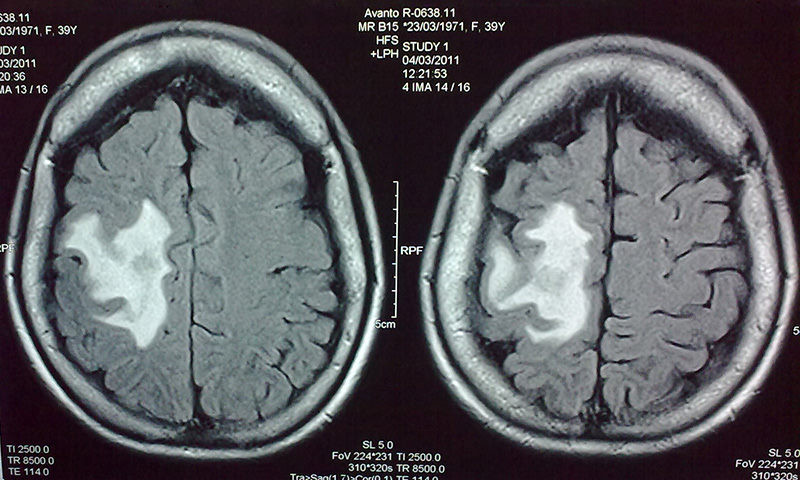

Casos Neuroloquirúrgicos

Envíado por Dr. Ruben Eduardo Amaya Contreras